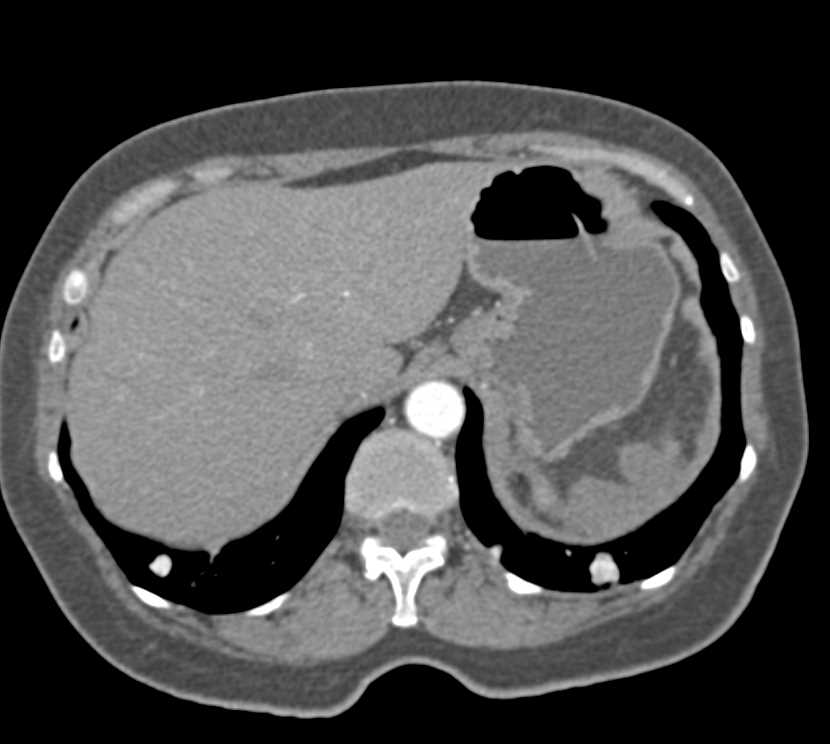

Metastatic Renal Cell Carcinoma with Rib Metastases